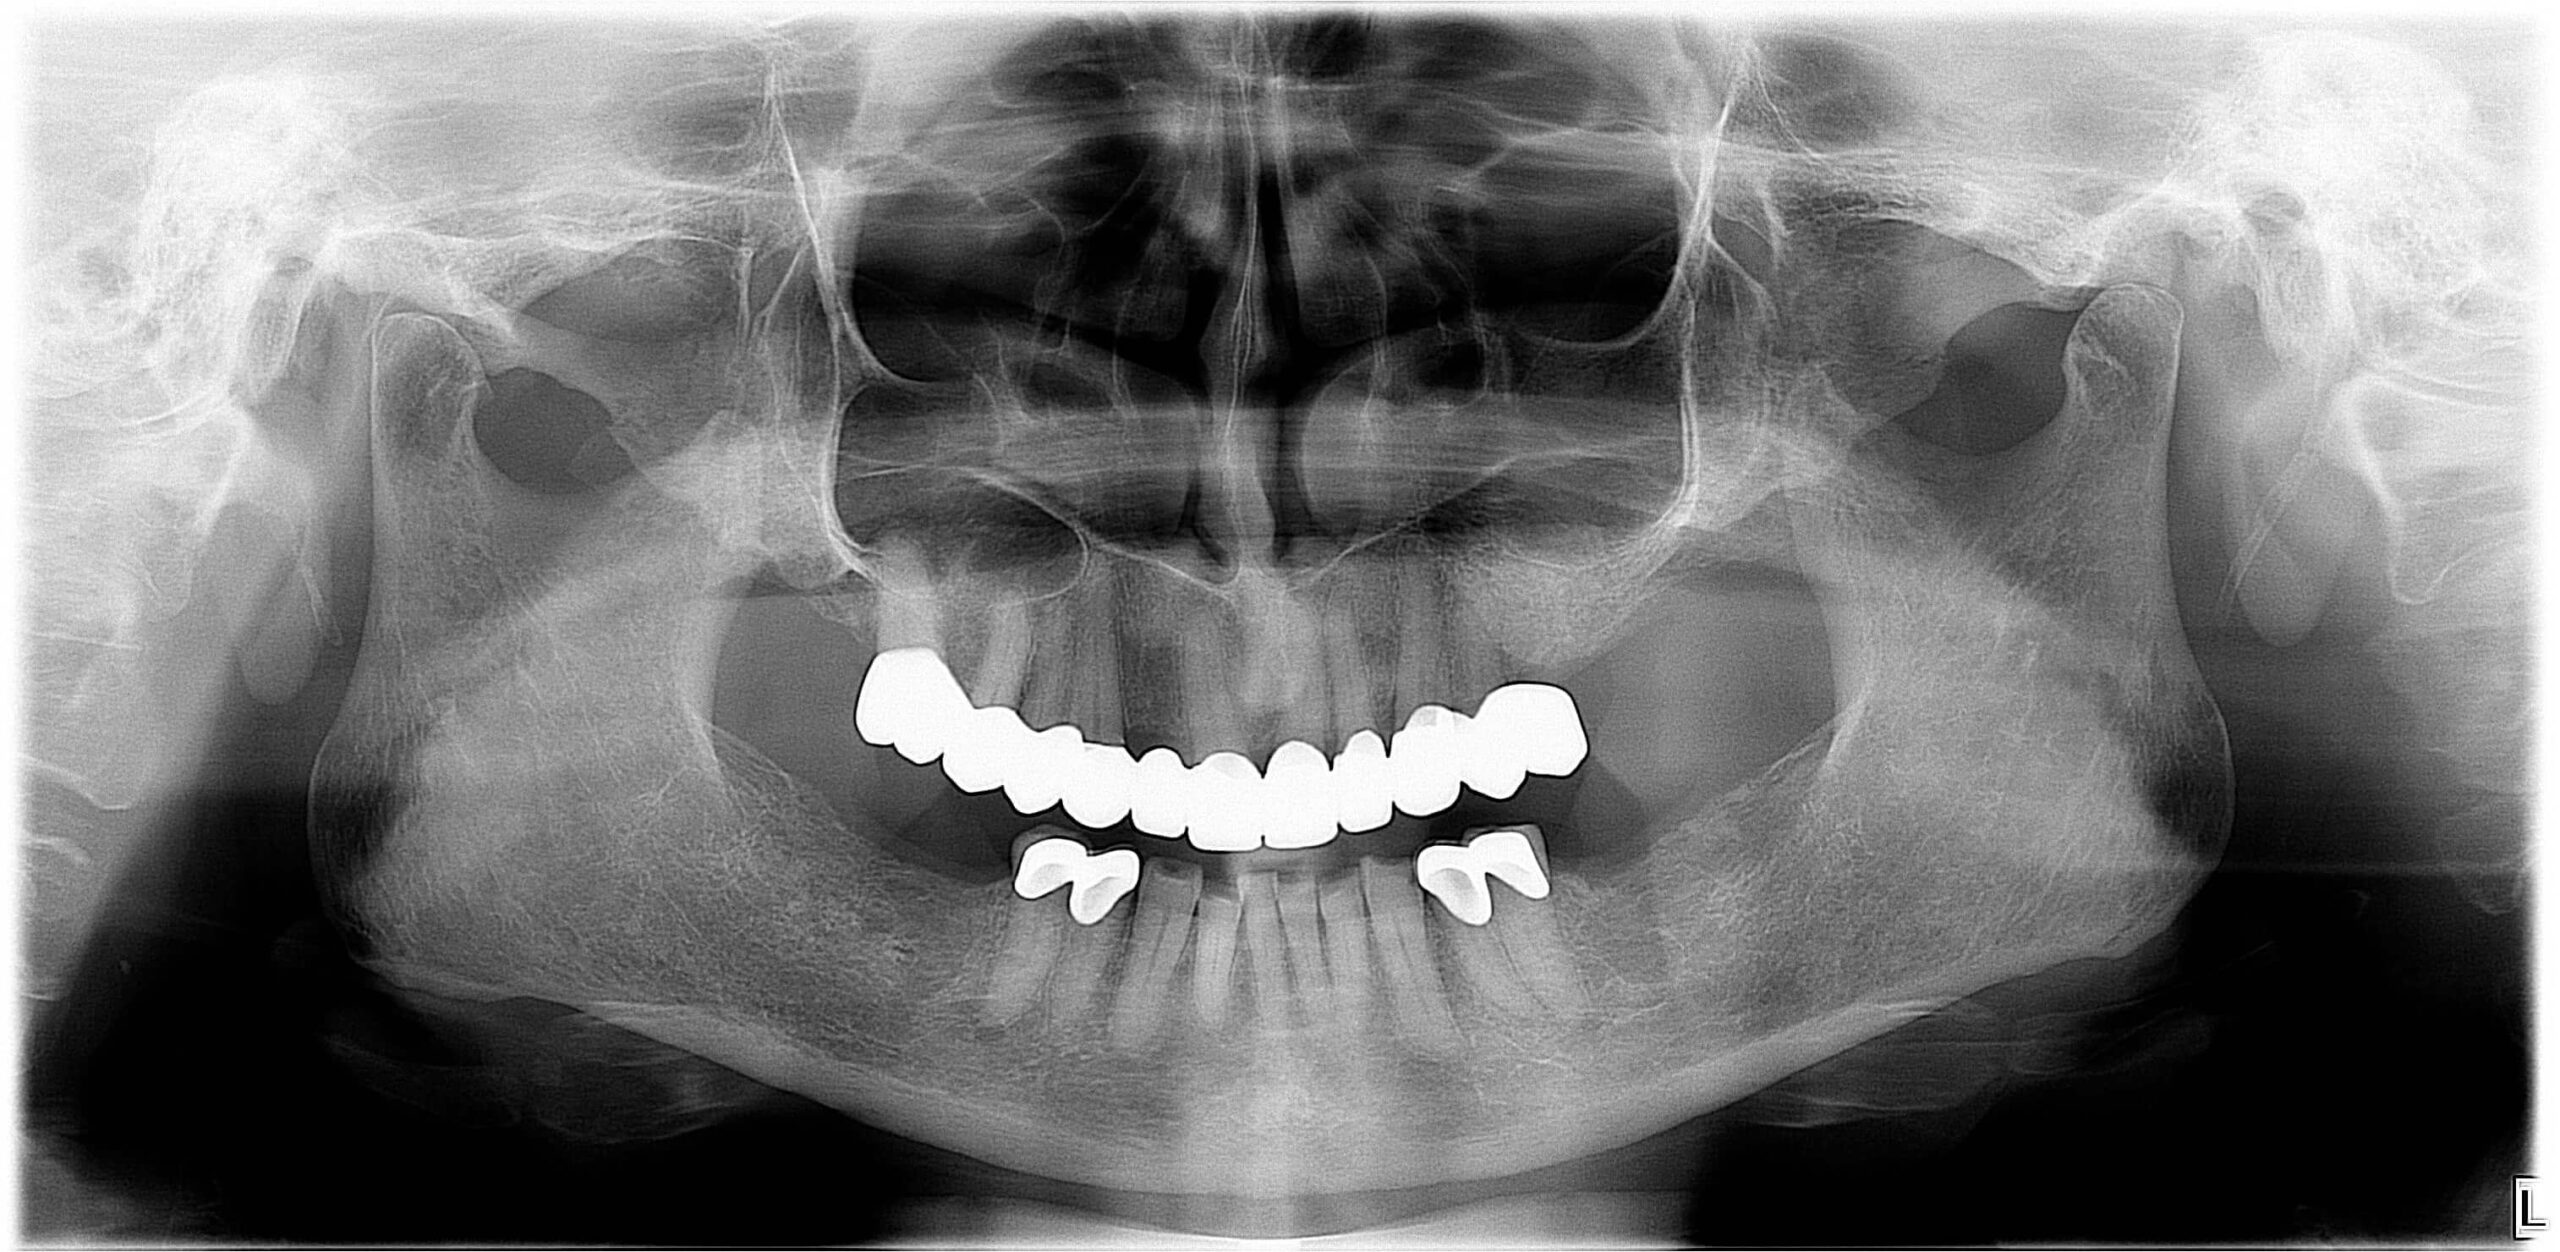

2. Fogászati eredetű fájdalmak

A fogak és az állkapocs közeli kapcsolatban állnak egymással, így számos fogászati probléma válthat ki állkapocsfájdalmat:

- Fogfájás: például gyökércsatorna-gyulladás vagy tályog

- Foghúzás utáni szövődmények: gyulladás, fertőzés, száraz fogmeder

- Bölcsességfog: különösen az előtörés során vagy a ferdén nőtt bölcsességfogak nyomása esetén alakulhat ki állkapocscsont fájdalom

- Nem megfelelően kialakított fogpótlások: rosszul illeszkedő koronák, hidak vagy kivehető pótlások hosszú távon megváltoztathatják a harapási viszonyokat, túlterhelhetik az állkapocsízületet, és funkcionális egyensúlyzavart idézhetnek elő. Ez gyakran vezet feszüléshez, rágás közbeni fájdalomhoz vagy ízületi kattogáshoz.

Fogászati kezelés

- Fogtályog, szuvas fog, gyulladás vagy foghúzás utáni komplikáció esetén antibiotikumos kezelés, gyökérkezelés vagy sebészi beavatkozás lehet szükséges

- Bölcsességfog okozta fájdalom esetén gyakran javasolt az érintett fog eltávolítása